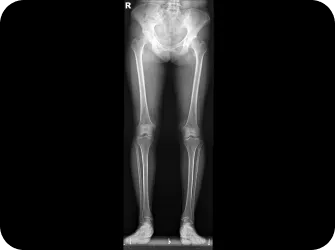

Catch Point 05. 전신불균형

안면비대칭을 악화시키는 전신 불균형을 같이 잡아라!

1. 머리뼈, 어깨뼈, 척추, 골반을 함께 교정

인체는 바이오링크에 의해 모두 연결되어 있습니다.

발목과 무릎처럼 서로 가까이서 영향을 주고 받기도 하지만

어깨뼈와 후두골, 천골(골반사이삼각형뼈)-목뼈2번-턱관절처럼

서로 멀리 떨어진 뼈들이 밀접하게 연관되어 움직이기도 합니다.

골반 틀어짐도 안면비대칭을 악화시키는 요인이 되기 때문에 비틀린 골반을 정상화하여 몸 전체의 축을 바로 잡으면 얼굴비대칭의 개선 뿐만 아니라 피로의 개선 및 목과 허리 골반통증 완화 효과도 있습니다.

안면비대칭에 절대적인 영향을 주는 턱관절과 후두골을 교정하기 위해 목뼈 2번 천골 및 어깨뼈를 함께 교정하는 기술이 꼭 필요합니다.

전신 엑스레이 검사

턱, 어깨 높이, 골반 틀어짐, 부정렬

다리길이 엑스레이 검사

다리 길이 차이에 의한 목과 안면비대칭 파악